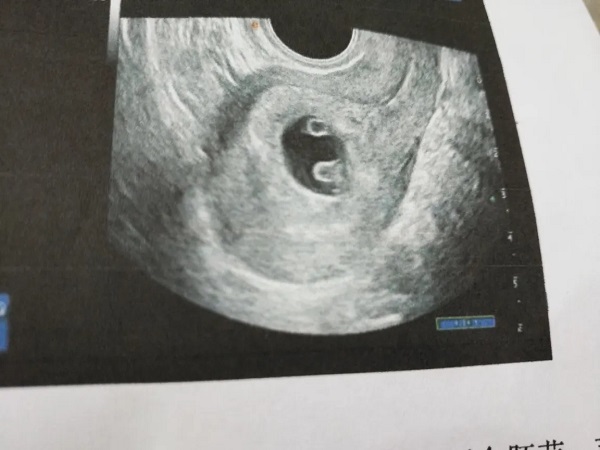

众所周知,女性每个月只有一个成熟的卵泡会从卵巢中排出,然后就会和男性的精子进行结合形成受精卵,并着床在子宫内膜上进而实现受孕。由于大多数女性都只有一个卵泡排出,因此自然怀上双胞胎的几率是非常低的。试管为了提高成功率都会进行促排卵治疗,主要是促进多个卵泡成熟,但是在提高试管成功率的同时也增加了多胎妊娠的几率。很多想要生双胎的女性就都会选择促排实现,但其实风险是非常大的,可能会导致卵巢过度刺激综合征,严重的还会影响女性的身体健康。

促排卵主要就是通过药物刺激卵巢中激素的分泌进而促使多个卵泡同时生长发育直到成熟,这样就能够获得更多数量的优质卵泡配成胚胎。促排卵是试管婴儿治疗中必不可少的一个过程,有很多想要生育双胞胎的患者就想要通过促排的方式来实现。通过促排怀双胞胎其实是非常危险的,可能会导致女性排卵异常,而且多胎妊娠的风险也是非常大的,因此并不建议大家通过这样的方式来生育双胎。

通过促排卵服用了促排药物之后就能够促进卵泡的生长发育,进而就会有两个甚至是三个卵泡排出,就大大提高了女性怀上双胎生殖是多胎的几率。但是需要知道的是,促排怀双胎的风险是比较大的,可能会对女性的身体造成伤害。